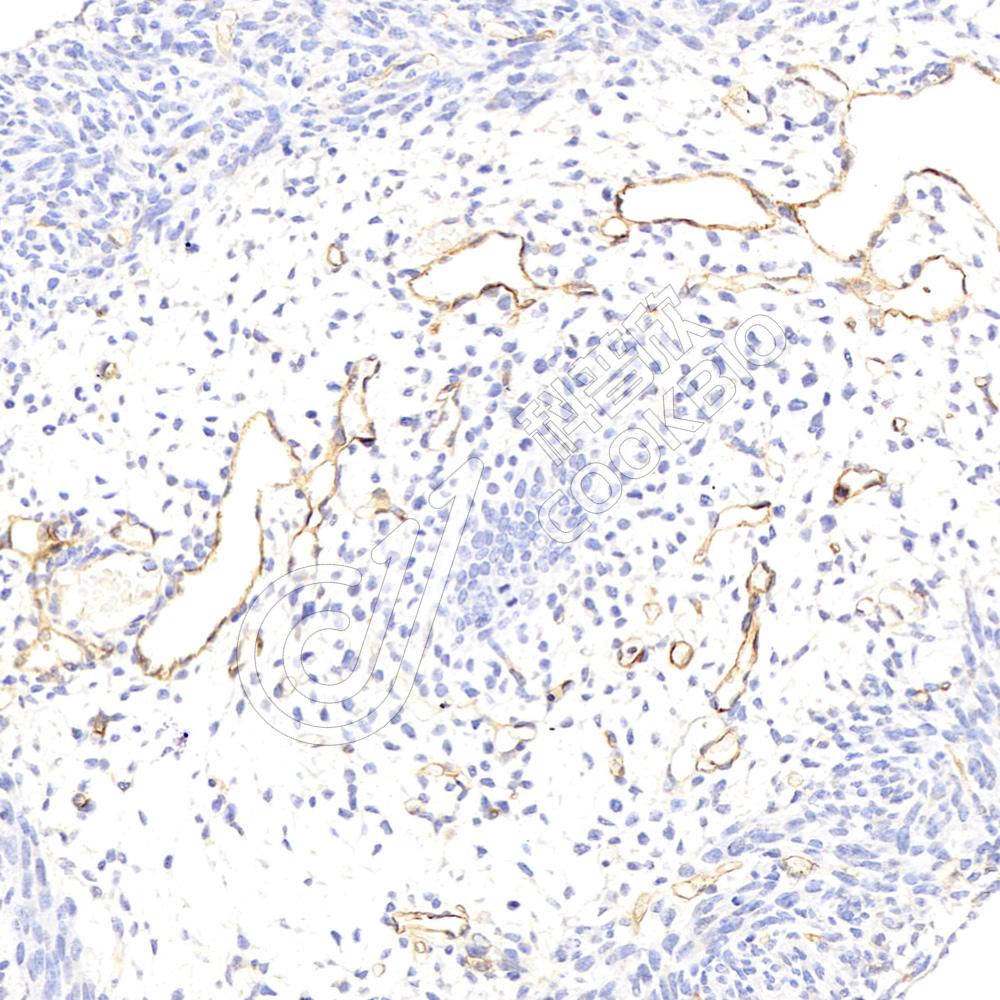

IHC/IF 免疫组织化学/免疫荧光

物种:小鼠,大鼠

稀释比:1:200-1:400

阳性样品:—